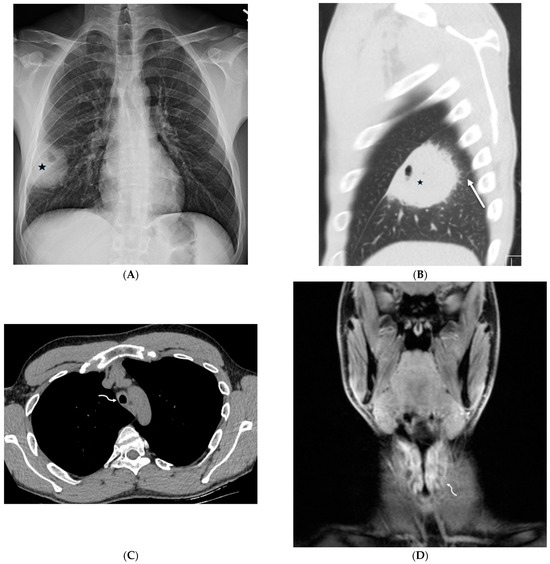

5.2. Kaposi’s Sarcoma

- Gasparetto, T.D.; Marchiori, E.; Lourenço, S.; Zanetti, G.; Vianna, A.D.; Santos, A.A.; Nobre, L.F. Pulmonary involvement in Kaposi sarcoma: Correlation between imaging and pathology. Orphanet J. Rare Dis. 2009, 4, 18. [Google Scholar] [CrossRef]

| Kaposi’s sarcoma | nodular | + | + | + | − | − | + | − | − | + |

| Kaposi sarcoma | Associated with HIV infection | Cutaneous lesions, mucosal involvement, lytic bone lesions, nodular lesions in the liver and spleen |